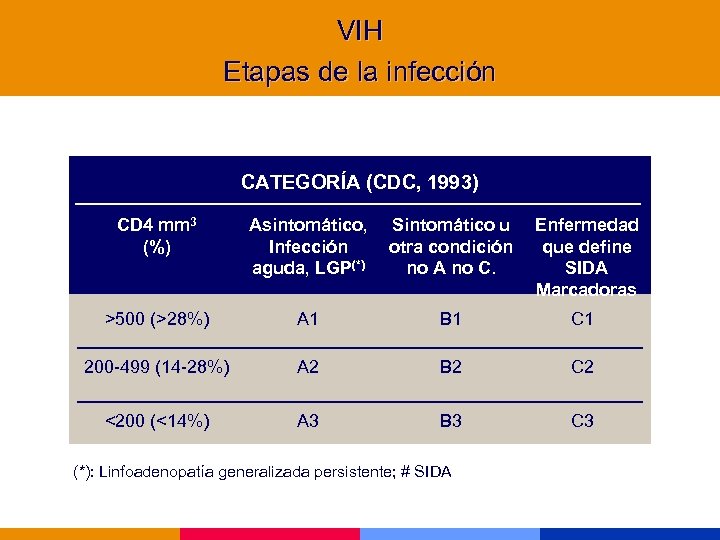

VIH Etapas de la infección CATEGORÍA (CDC, 1993) CD 4 mm 3 (%) Asintomático, Infección aguda, LGP(*) Sintomático u otra condición no A no C. Enfermedad que define SIDA Marcadoras >500 (>28%) A 1 B 1 C 1 200 -499 (14 -28%) A 2 B 2 C 2 <200 (<14%) A 3 B 3 C 3 (*): Linfoadenopatía generalizada persistente; # SIDA

VIH Etapas de la infección CATEGORÍA (CDC, 1993) CD 4 mm 3 (%) Asintomático, Infección aguda, LGP(*) Sintomático u otra condición no A no C. Enfermedad que define SIDA Marcadoras >500 (>28%) A 1 B 1 C 1 200 -499 (14 -28%) A 2 B 2 C 2 <200 (<14%) A 3 B 3 C 3 (*): Linfoadenopatía generalizada persistente; # SIDA